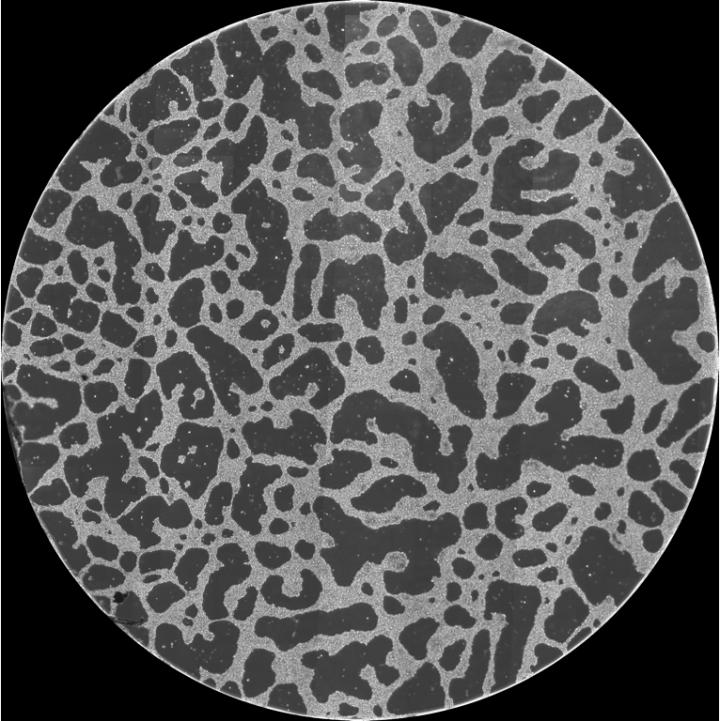

image: A large-scale network structure formed in vitro by cancer cells. The diameter of the image is 14 mm.

Osaka, Japan - Cancer cells are known to migrate and collaborate to form networks that function as conduits providing access to nutrients and blood vessels. Now, researchers in Japan have generated similar large-scale structures from cancer cells in the laboratory and thus gained a better understanding of the underlying forces and their interactions.

The research team first cultured HeLa cells, a strain of epithelial-like cervical cancer cells, on Matrigel, a gelatinous protein mixture resembling the extracellular environment of many tissues, and showed that the cells migrate aggressively and form large-scale structures. This was previously difficult to achieve in vitro as HeLa cells are relatively non-motile on glass. Using time-lapse imaging they analyzed the cell migration patterns and quantified the large-scale structures with a two-point correlation function.

"We observed that HeLa cells first exhibited increased motility on Matrigel, which later decreased after they integrated into a spatially distinct structure," explains Dr. Tokuko Haraguchi, senior researcher at NICT. "We also noted that HeLa cells in close proximity formed bridges between cell aggregates, and that structures were formed in a cell-density dependent manner."

To explain these results, the researchers developed a simulated model in which cells migrate and interact using two distinct forces: remote forces that act at a distance through substrate deformation, and contact forces between cells in physical proximity. By selectively enabling these forces, they modelled the three types of structures formed—islands, network-like structures and continents—according to cell density.